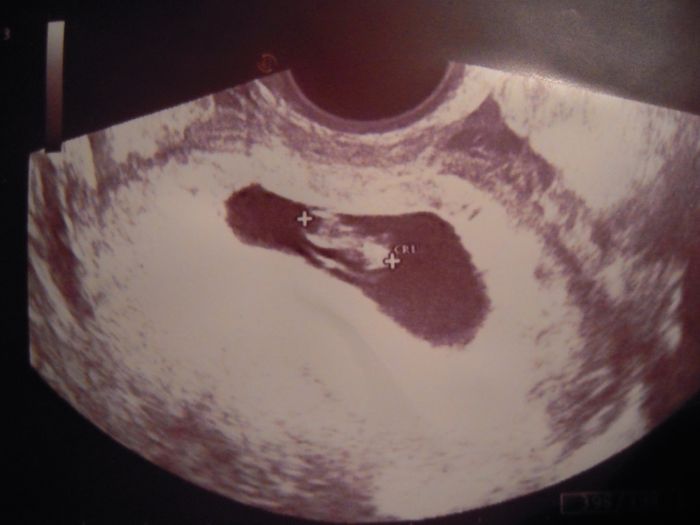

Doufám, že vše bude ok a večer vám přihodím fotečku z ultrazvuku